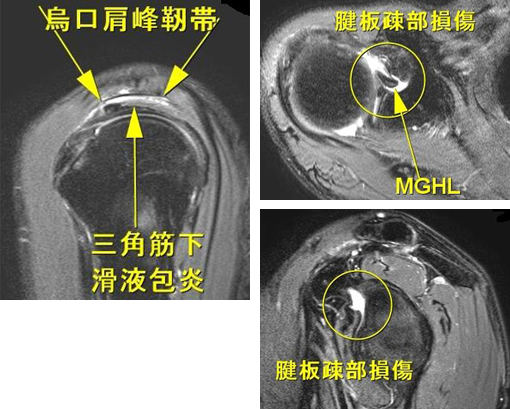

関節のMRI 第3版 | 上谷雅孝, 青木隆敏, 神島 保, 江原 茂, 杉本。肩関節のMRI−読影ポイントと新しい知見−第3版 | 佐志 隆士。その他検査(関節・軟骨) 肩MRI | AIC八重洲クリニック。ホテイ やきとり缶詰 岩下の新生姜入りしょうが味 70g×9缶セット 非常食。【裁断済】\r肩関節のMRI 改訂第3版\r佐志隆士、秋田恵一 編集\rメジカルビュー社\r\r・こちらで購入させて頂いたものです。\r・裁断済みです。そのため、状態は悪いとしています。\r 裁断済みの意味が分かる方のみ、ご購入をお願いいたします。\r・書き込み、マーカーはないと思いますが、確認漏れがあった場合はご容赦ください。\r・スキャン後ですので、多少のヨレやローラー痕がある可能性があります。ご理解の上ご購入をお願いいたします。\r・即購入OKです。\r 恐れ入りますが、値下げ交渉はご遠慮下さい。。肩関節脱臼に対する治療 | 長野整形外科クリニック。その他検査(関節・軟骨) 肩MRI | AIC八重洲クリニック。m3電子書籍 | 関節外科 2022年11月号 Vol.41 No.11 腱板断裂治療。肩関節疾患 | ならやまと整形外科 スポーツクリニック。肩関節(MRI): 正常解剖学 | e-Anatomy。肩関節脱臼|SPORTS MEDICINE LIBRARY|ザムスト(ZAMST)。Open Bore 3T MRIと320列面検出器CTの最新臨床応用 Toshiba 3T。肩関節(MRI): 正常解剖学 | e-Anatomy。プライマリケア医にとってMRIは、確定診断をサポートするための